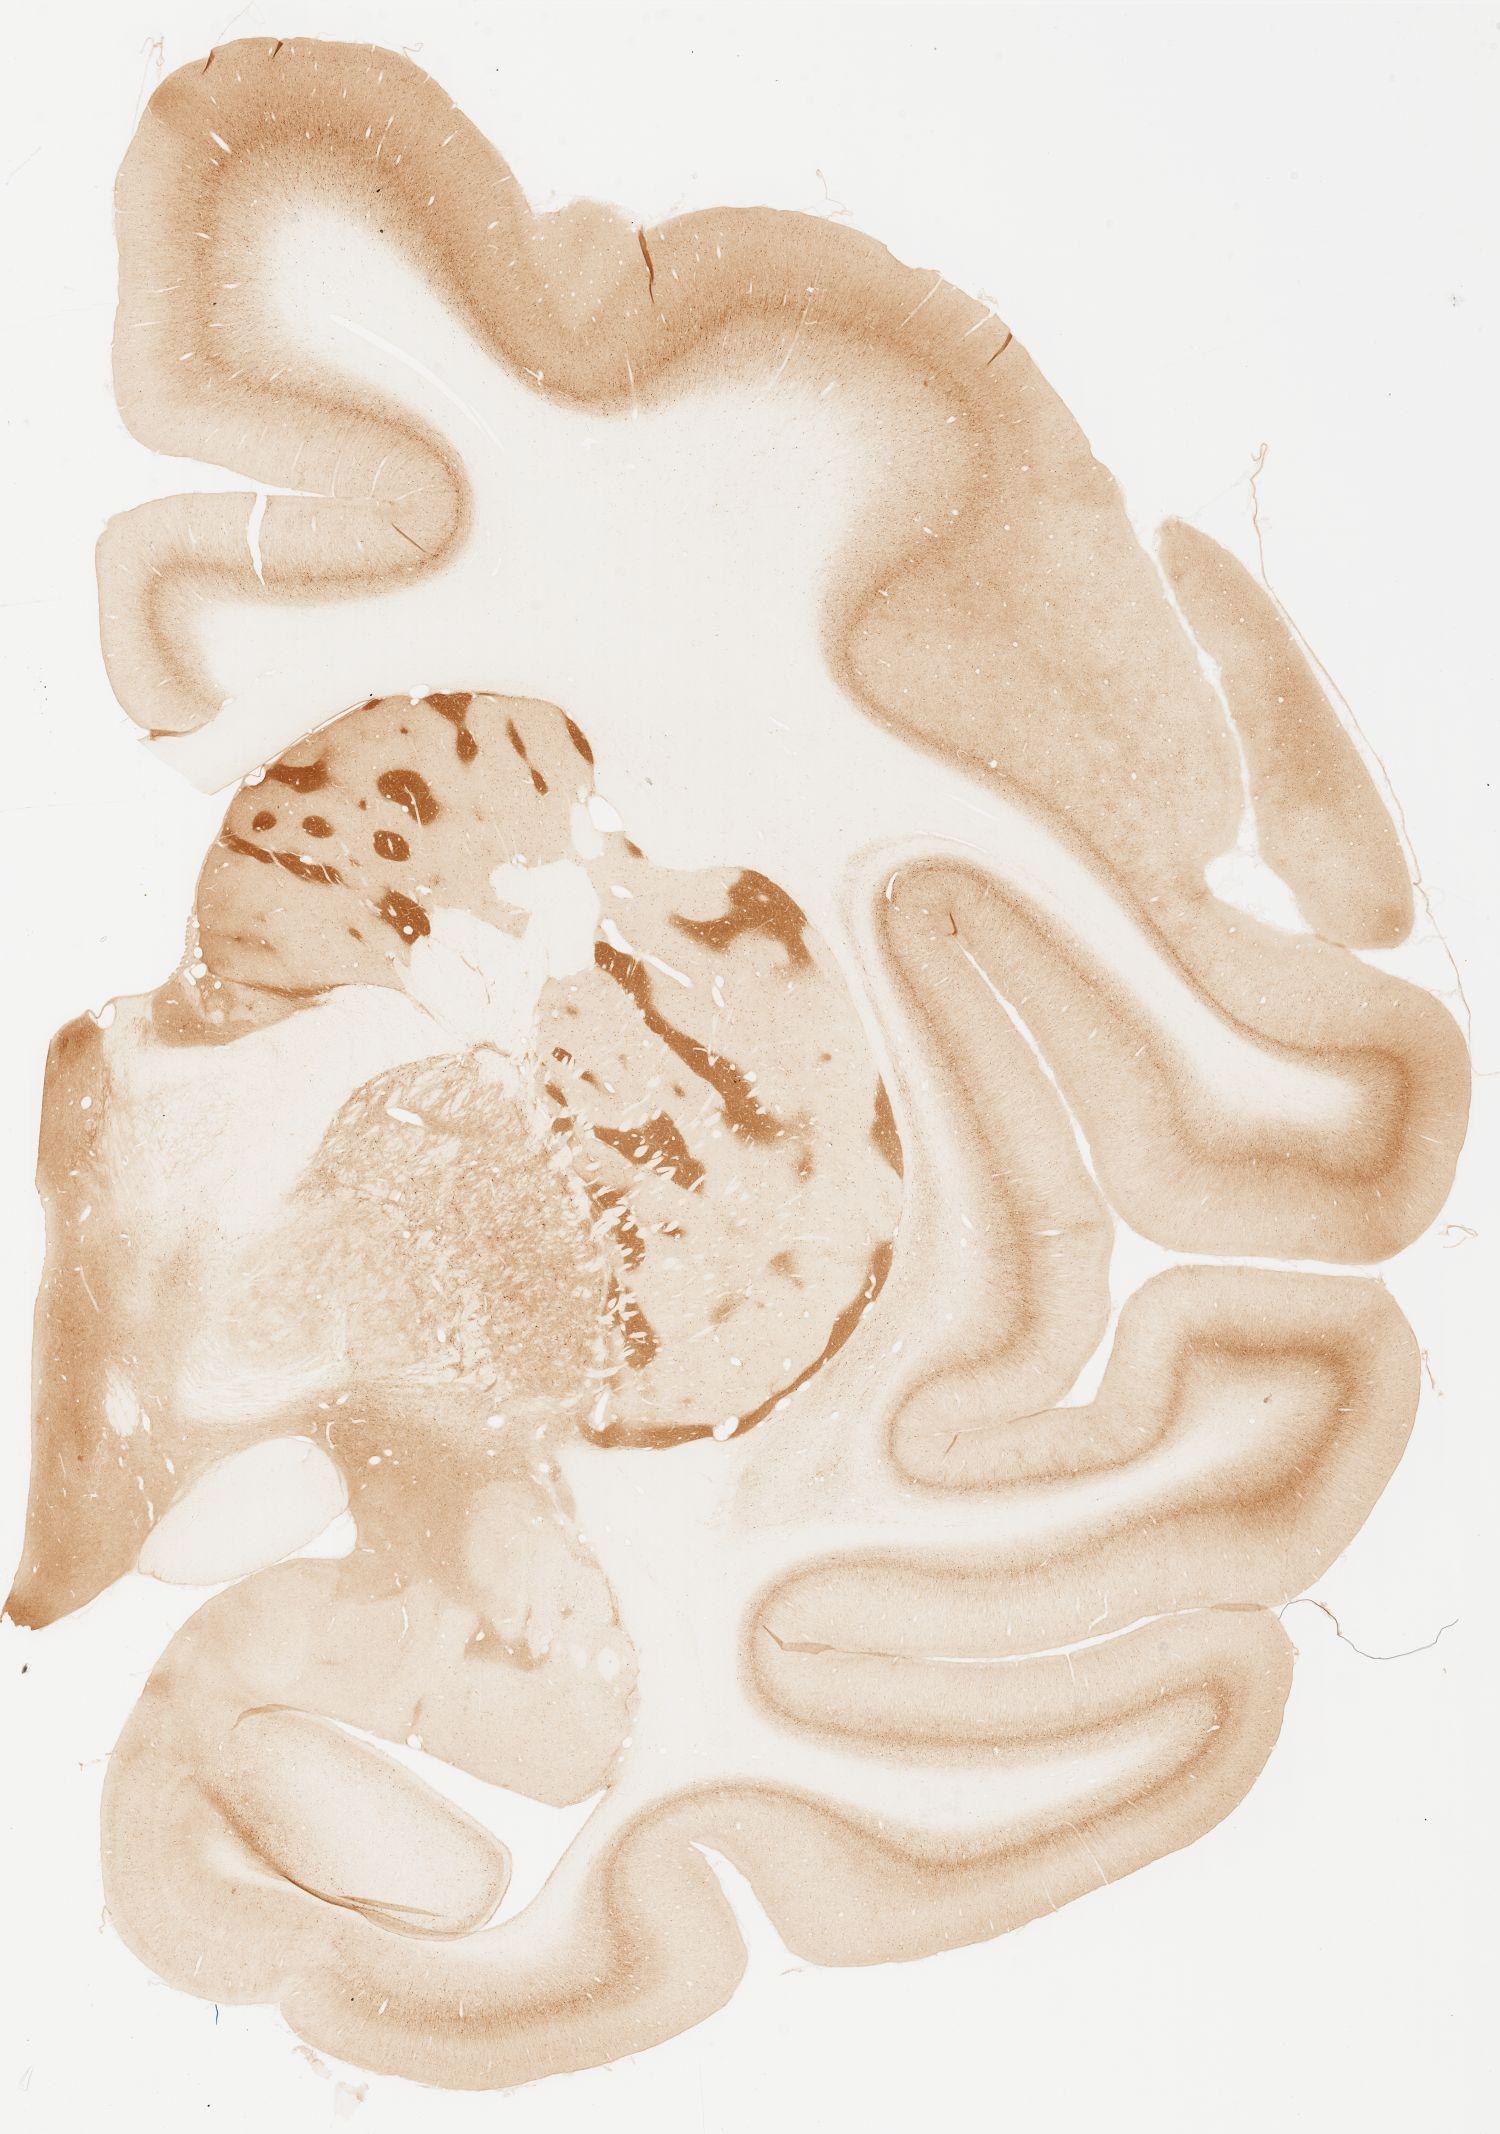

Datasets -> Macaca Fascicularis -> KChIP1, (Potassium Voltage-Gated Channel-Interacting Protein 1), coronal, immuno, Whole-Brain, adult

[ Metadata ]   ·   Source: Edward G. Jones

Displaying Sections 41 thru 80 of 92 Sections for this Dataset